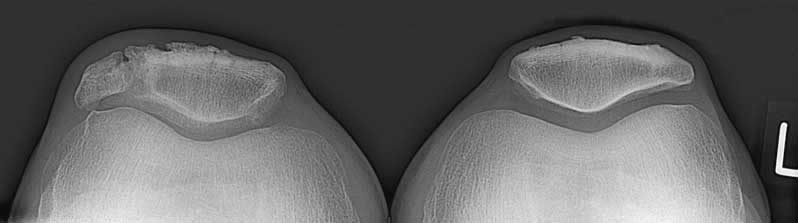

June 2004 I fell on my right knee. After four months most pain was gone but something remained. Now X-ray photographs made clear that I have a 'patella bipartita', that is a patella/knee-cap that exist of two parts. I up to now did not know that! I only knew that the right patella is a mega patella.

Because pictures of a patella bipartita are difficult to find I place the pictures on the web (pictures made in 'Diaconessenhuis' in Zeist, The Netherlands). Most spectacular is viewing like this:

You see the right patella on the left, it exists of two parts and is big on the outside.